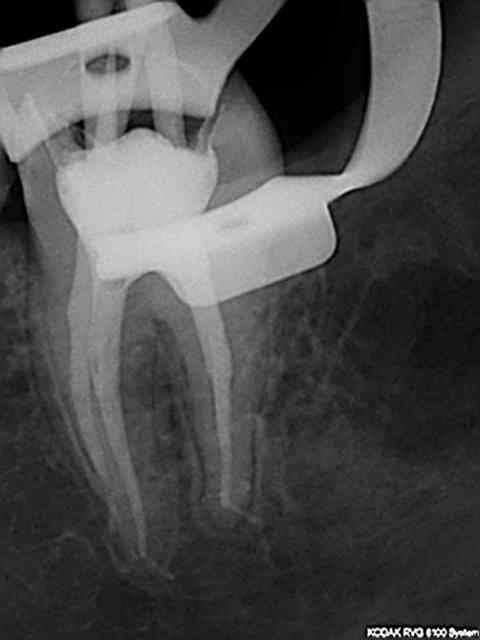

J'ai utilisé le localisateur d'apex , mais bon un radio c'est une radio ...)))

J'ai fait une reprise de TR sur 27 en novembre dernier ; digue, javel, NiTi, pour un bon résultat radio.

Aucun problème de symptomatologie, radio argentique et numérique OK, et découverte forfuite d'un kyste énorme sur la racine vestibulaire de cette dent lors d'un scan pour implant en place de 37.

Radio cone 25 en place etc....)))) j'avoue je pèche dans le etc !)))